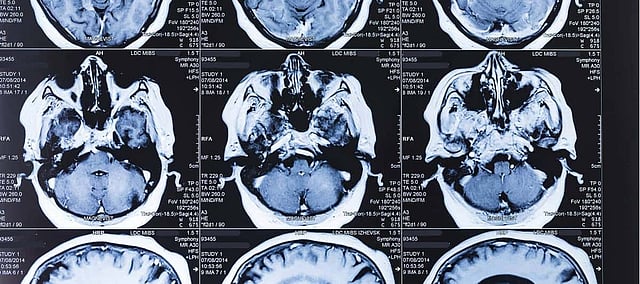

A latest published report found that Artificial Intelligence can at best be equivalent to human experts when it comes to making image-based medical diagnoses. Today, AI research within medicine is growing rapidly and it has the potential to transform the medical research from the bottom. Experts say it will ease the strain on resources, free up time for physician-patient interactions as well as aid in tailored diagnoses.

Since the sector is overwhelmed by impecunious research, the latest findings are based on a few numbers of studies. And the researchers found one of the burgeoning applications is the use of AI in medical images, a field relies on Deep Learning, wherein a series of labelled images are fed into algorithms that pull-out features within them and learn how to classify similar images.

This approach has shown promise in disease treatment, from eye conditions to cancer. However, responding to questions on how such deep learning systems measure up to human skills, researchers conducted the first comprehensive review of published studies on the issue that revealed humans and machine are on a par.

Afterward, the team pooled up the most promising results from each of the 14 studies that found deep learning systems correctly detected a disease state 87% of the time, compared with 86% for healthcare professionals, as well as correctly gave the all-clear 93% of the time that outperformed the human experts with 91%.

With these outcomes, Denniston is very optimistic about the potential of AI in healthcare, with saying such deep learning systems could perform as a diagnostic tool and assist in tackling the backlog of scans and images. In the same context, Liu said such systems could prove useful in places which lack experts to interpret images. It would be significant to leverage deep learning systems in clinical trials to weigh, whether patient outcomes improved compared with current practices.